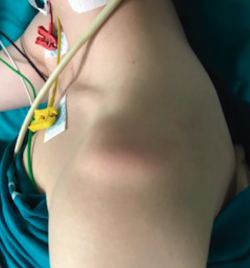

The procedure is generally performed under general anesthesia and brachial plexus block. It is advisable to carry out an exploration of the shoulder under anesthesia, since this allows us to evaluate the glenohumeral joint with muscle relaxation and clinically confirm the instability, as well as its type and grade.